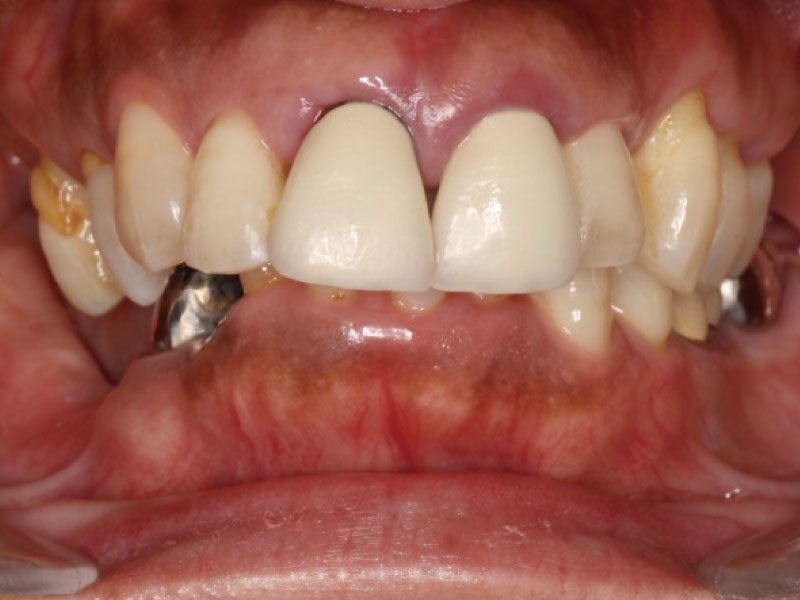

重度歯周病患者様の治療前、治療後ビフォー